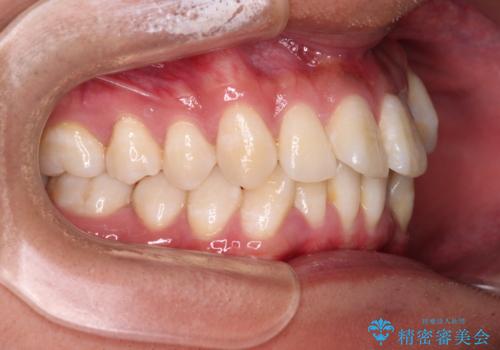

歯列としてはインビザラインでもワイヤー矯正でも対応できるものでしたが、上顎の八重歯や下顎小臼歯の捻転といったインビザラインでは時間のかかってしまう歯列不正が認められたため、補助装置やワイヤー矯正を治療当初に使用することで、インビザラインによる治療をスムーズに行えるように計画しました。

インビザラインは得意・不得意の差がはっきりとしているため、ワイヤー装置などをうまく活用することで、治療期間を短縮するとともに、より理想的な仕上がりを達成することができます。